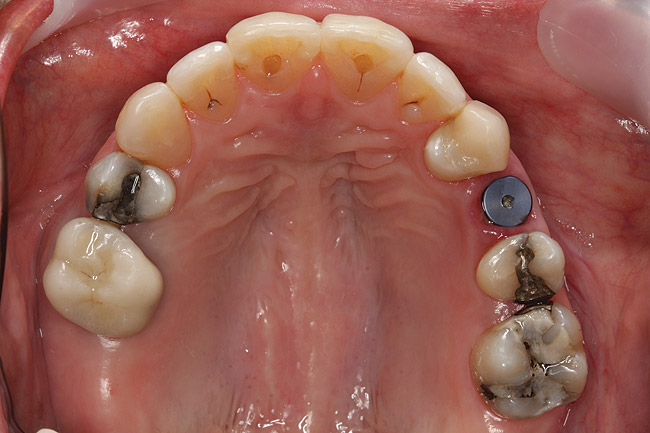

Fig 29 (through Fig 32). Jackscrews were activated 0.5 mm/day after 5-day latency period. Note pure translation of segments without tipping. Result 8 months postsurgery. Tooth No. 12 was converted to a canine, and an implant was placed in regenerate bone. Note amount of alveoloskeletal correction and increase in volume of maxillary arch. Also note the amount of protraction of maxillary anterior segments while anchorage was maintained in posterior segment. Restorative dentist: Michael E. Carter, DDS.

Fig 30. Jackscrews were activated 0.5 mm/day after 5-day latency period. Note pure translation of segments without tipping. Result 8 months postsurgery. Tooth No. 12 was converted to a canine, and an implant was placed in regenerate bone. Note amount of alveoloskeletal correction and increase in volume of maxillary arch. Also note the amount of protraction of maxillary anterior segments while anchorage was maintained in posterior segment. Restorative dentist: Michael E. Carter, DDS.

Figure 30

Fig 31. Jackscrews were activated 0.5 mm/day after 5-day latency period. Note pure translation of segments without tipping. Result 8 months postsurgery. Tooth No. 12 was converted to a canine, and an implant was placed in regenerate bone. Note amount of alveoloskeletal correction and increase in volume of maxillary arch. Also note the amount of protraction of maxillary anterior segments while anchorage was maintained in posterior segment. Restorative dentist: Michael E. Carter, DDS.

Figure 31

Fig 32. Jackscrews were activated 0.5 mm/day after 5-day latency period. Note pure translation of segments without tipping. Result 8 months postsurgery. Tooth No. 12 was converted to a canine, and an implant was placed in regenerate bone. Note amount of alveoloskeletal correction and increase in volume of maxillary arch. Also note the amount of protraction of maxillary anterior segments while anchorage was maintained in posterior segment. Restorative dentist: Michael E. Carter, DDS.